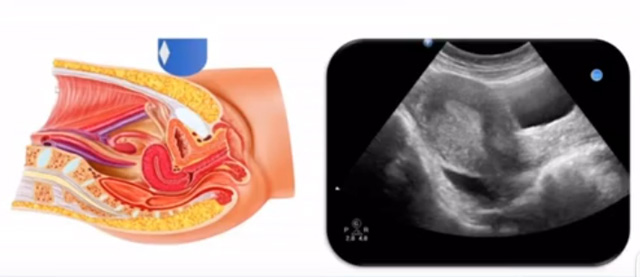

女性生殖系統(tǒng)包括內(nèi)、外生殖器官及其相關(guān)組織以及鄰近器官,其中內(nèi)生殖器是我們超聲檢查的主要對象。那么內(nèi)生殖器包括陰道、子宮還有輸卵管及卵巢。輸卵管及卵巢稱為子宮附件。子宮是倒置梨形,但是它是空腔厚壁肌性器官。它的正常值在育齡婦女。超聲探頭放在貼近腹壁盆腔上面位置,來看這個子宮在超聲上面的表現(xiàn)。從輪廓上來講,和示意圖是一樣的。這就是在超聲上面顯示的一個子宮的圖片。子宮在不同的時期與子宮頸的比例。成年婦女指的是育齡婦女為2:1子宮體是比較大的,嬰兒期為1:2說明宮頸比較大,絕經(jīng)期1:1。所以我們在看到子宮圖時候可以根據(jù)宮體宮頸比例大致可以推測屬于哪個時期的婦女。另外還可以根據(jù)比例大小來推斷是一個正常子宮還是異常子宮。

子宮從外到內(nèi),漿膜層、肌層、粘膜層。宮體部宮頸為梭形結(jié)構(gòu)。宮腔為上寬下窄的三角形,連接為峽部。子宮有什么功能呢?月經(jīng)血產(chǎn)生跟排出通道,精子運(yùn)行通道受精作用。囊胚著床及胎兒發(fā)育、生長的場所。分娩時產(chǎn)生宮縮使胎兒、胎盤娩出。未孕的子宮是很小的,已孕子宮就非常大,平均胎兒都有6斤重。所以這個后壁就體現(xiàn)出來。輸卵管由子宮角部向外延伸,為一對細(xì)長而彎曲的管道,呈管狀中空結(jié)構(gòu),大概長度是8-14厘米,粗1-4毫米,它的下方為卵巢和闊韌帶。間質(zhì)部是厚一點(diǎn)的,峽部是比較窄的地方,壺腹部,漏斗部。正常情況下,輸卵管在普通超聲DR難以顯示。